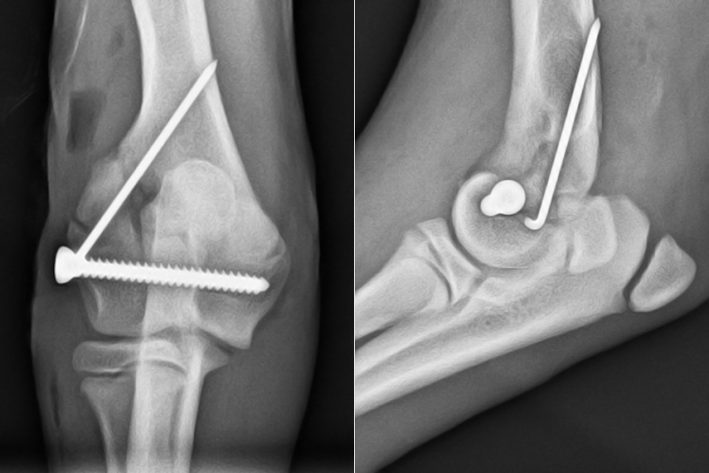

Ellenbogen nach der Operation – Versorgung mit einer Schraube und Pin